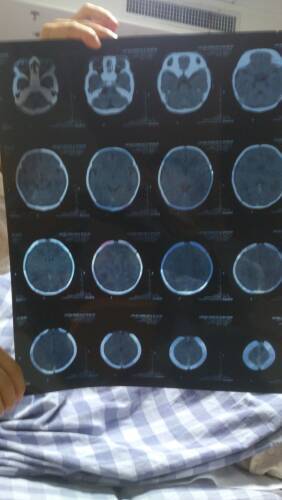

新生儿三天脑部CT诊断蛛网膜下腔出血,出生时有羊水浑浊现象,需要治疗吗?严重吗?医生建议脑部营养治 新生儿三天脑部CT诊断蛛网膜下腔出血,出生时有羊水浑浊现象,需要治疗吗?严重吗?医生建议脑部营养治疗。 点击展开 匿名用户 2013-11-22 18:08 为您推荐: 其他回答 病情分析: 你好,这种情况考虑还是严重的, 指导意见: 目前这个问题我建议及时的住院治疗观察吧,很重要的。 白其雨_6xwx 2013-11-22 18:16 相关问题 新生儿三天脑部CT诊断蛛网膜下腔出血,出生时有羊水浑浊现象,需要治疗吗?有人遇到此类现象吗?严重吗 新生儿脑部CT结果看不明白,请帮忙解释下,多谢 做脑部CT对新生儿有多大的辐射?